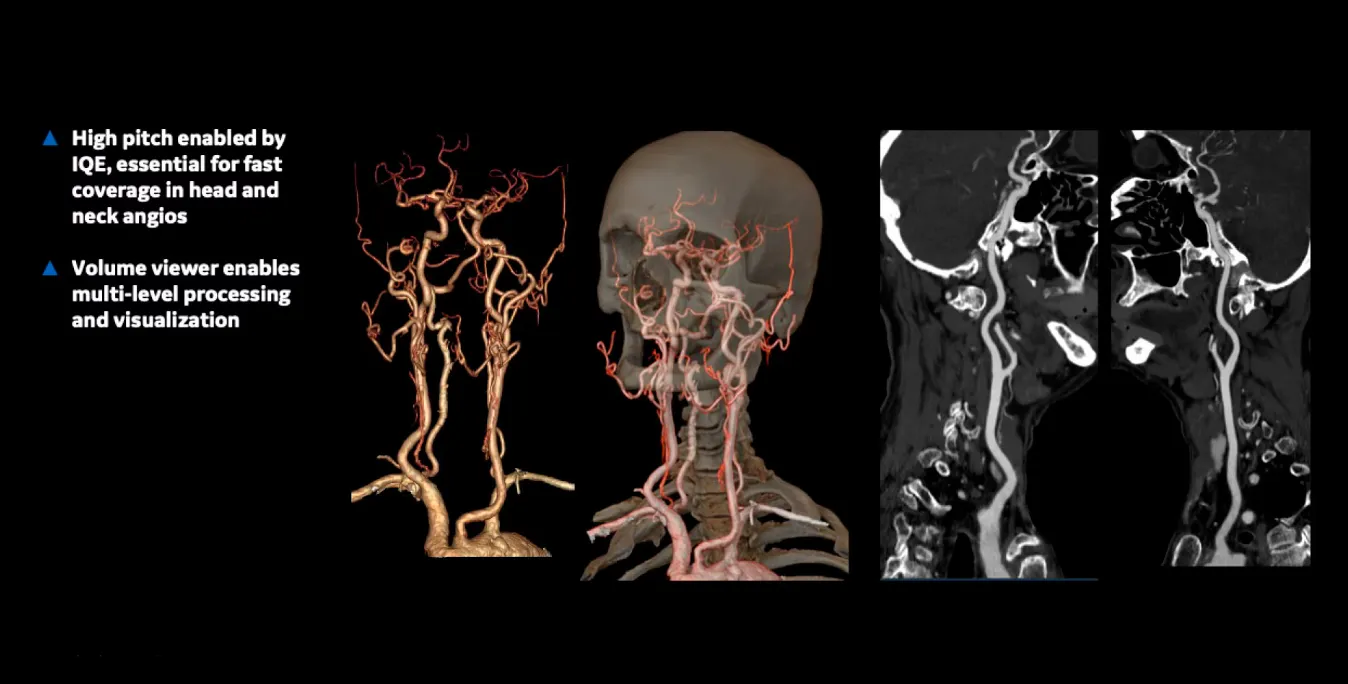

Клинические изображения

• Clarity Imaging Chain — комплексная цепочка визуализации для чётких и чистых изображений.

• IQE (Image Quality Enhancement) — улучшение качества изображения и снижение спиральных артефактов при тонких срезах.